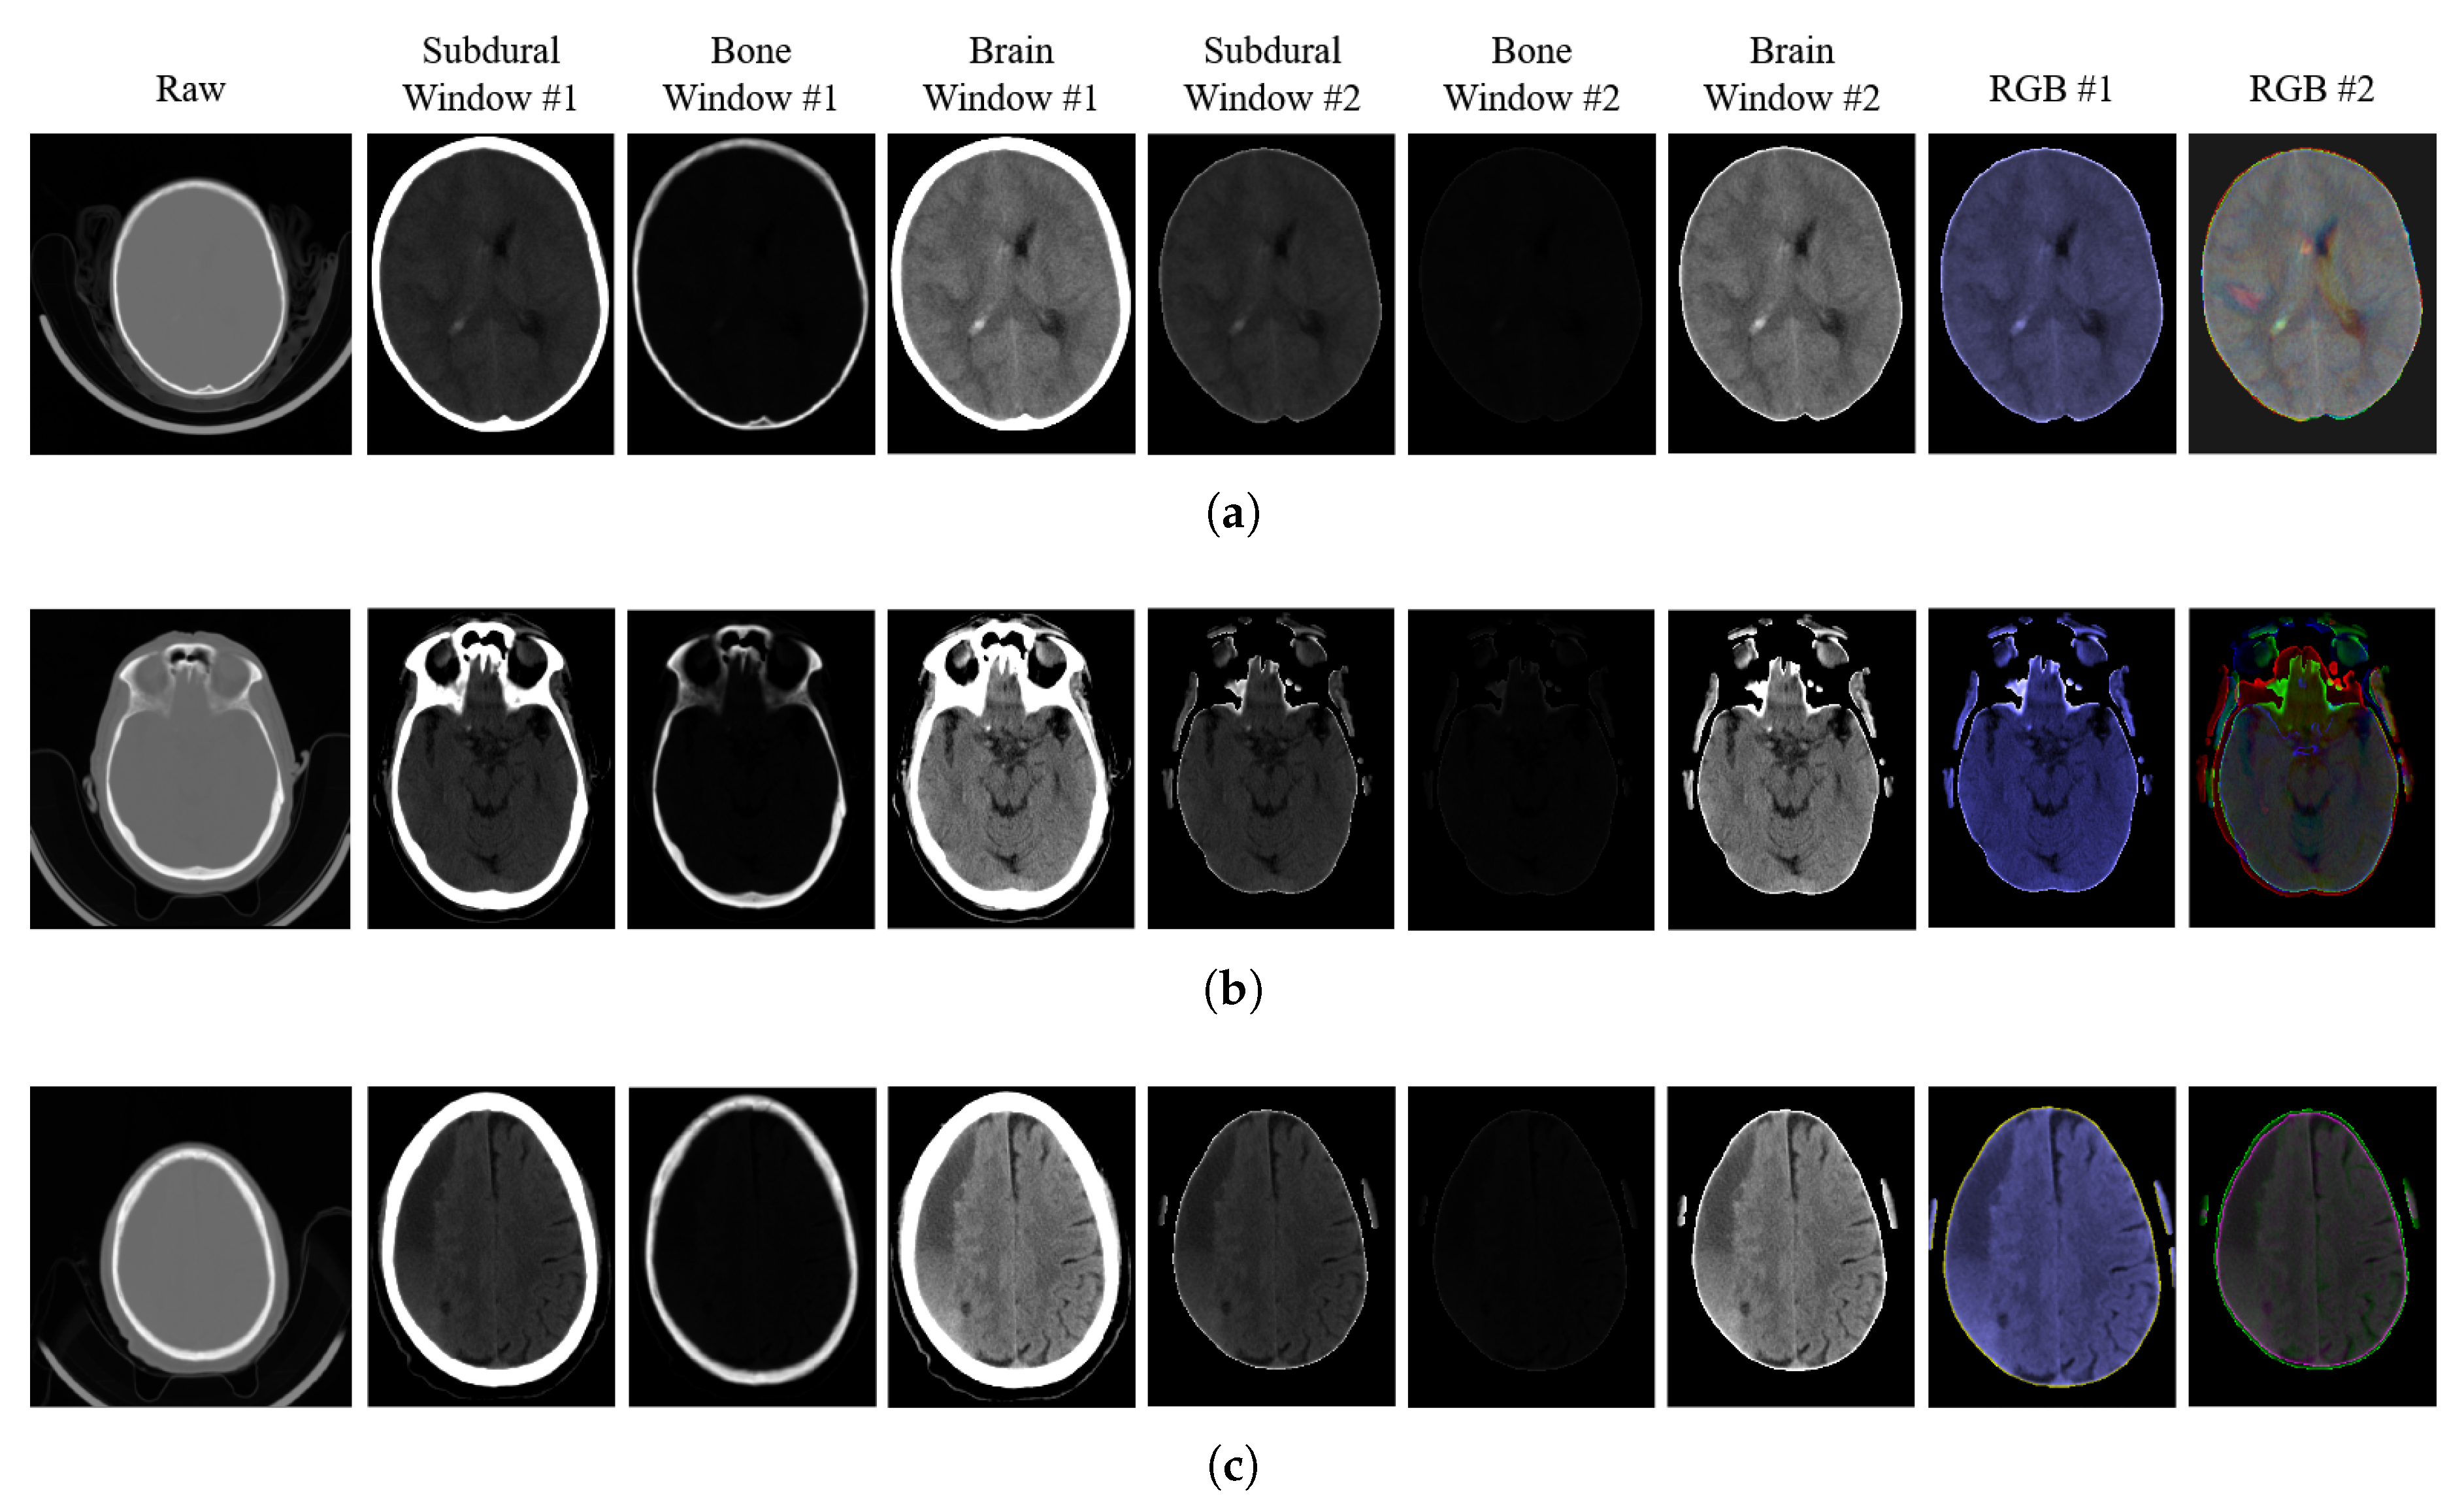

Applied Sciences Free Full Text Intracranial Hemorrhage Detection In Head Ct Using Double Branch Convolutional Neural Network Support Vector Machine And Random Forest Html